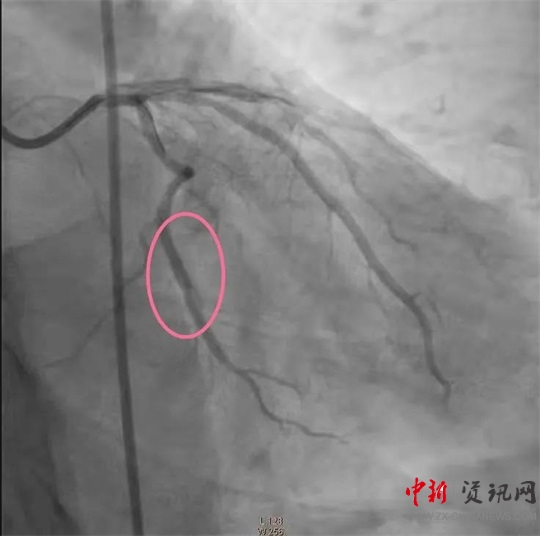

經(jīng)過一系列的術(shù)前準(zhǔn)備并經(jīng)患者家屬同意后,立即繞行病房進(jìn)入介入手術(shù)室,實(shí)施緊急手術(shù)。卒中中心團(tuán)隊(duì)、胸痛中心團(tuán)隊(duì)和介入團(tuán)隊(duì)密切配合,為患者分別實(shí)施了腦動(dòng)脈造影+主動(dòng)脈弓造影+顱內(nèi)動(dòng)脈瘤栓塞術(shù)+冠狀動(dòng)脈造影術(shù)+經(jīng)皮冠狀動(dòng)脈支架植入術(shù),成功把患者從死亡邊緣拉回。目前,患者病情穩(wěn)定,各項(xiàng)指標(biāo)良好。

(冠脈支架植入后)